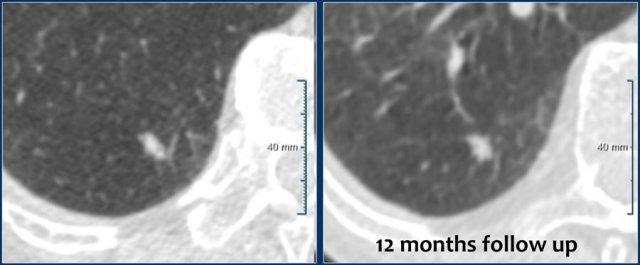

Hình ảnh cho thấy một nốt đặc đơn độc không có bờ tua gai kích thước 7 mm (162 mm3) ở thùy dưới phổi phải (RLL) của bệnh nhân nam 55 tuổi, không có tiền sử gia đình dương tính, nhưng có khí phế thũng nhẹ.

Theo dõi cho thấy sự ổn định dài hạn với kích thước 7 mm (146 mm3) tại thời điểm 12 tháng.

Bệnh nhân được kết thúc theo dõi bằng CT.